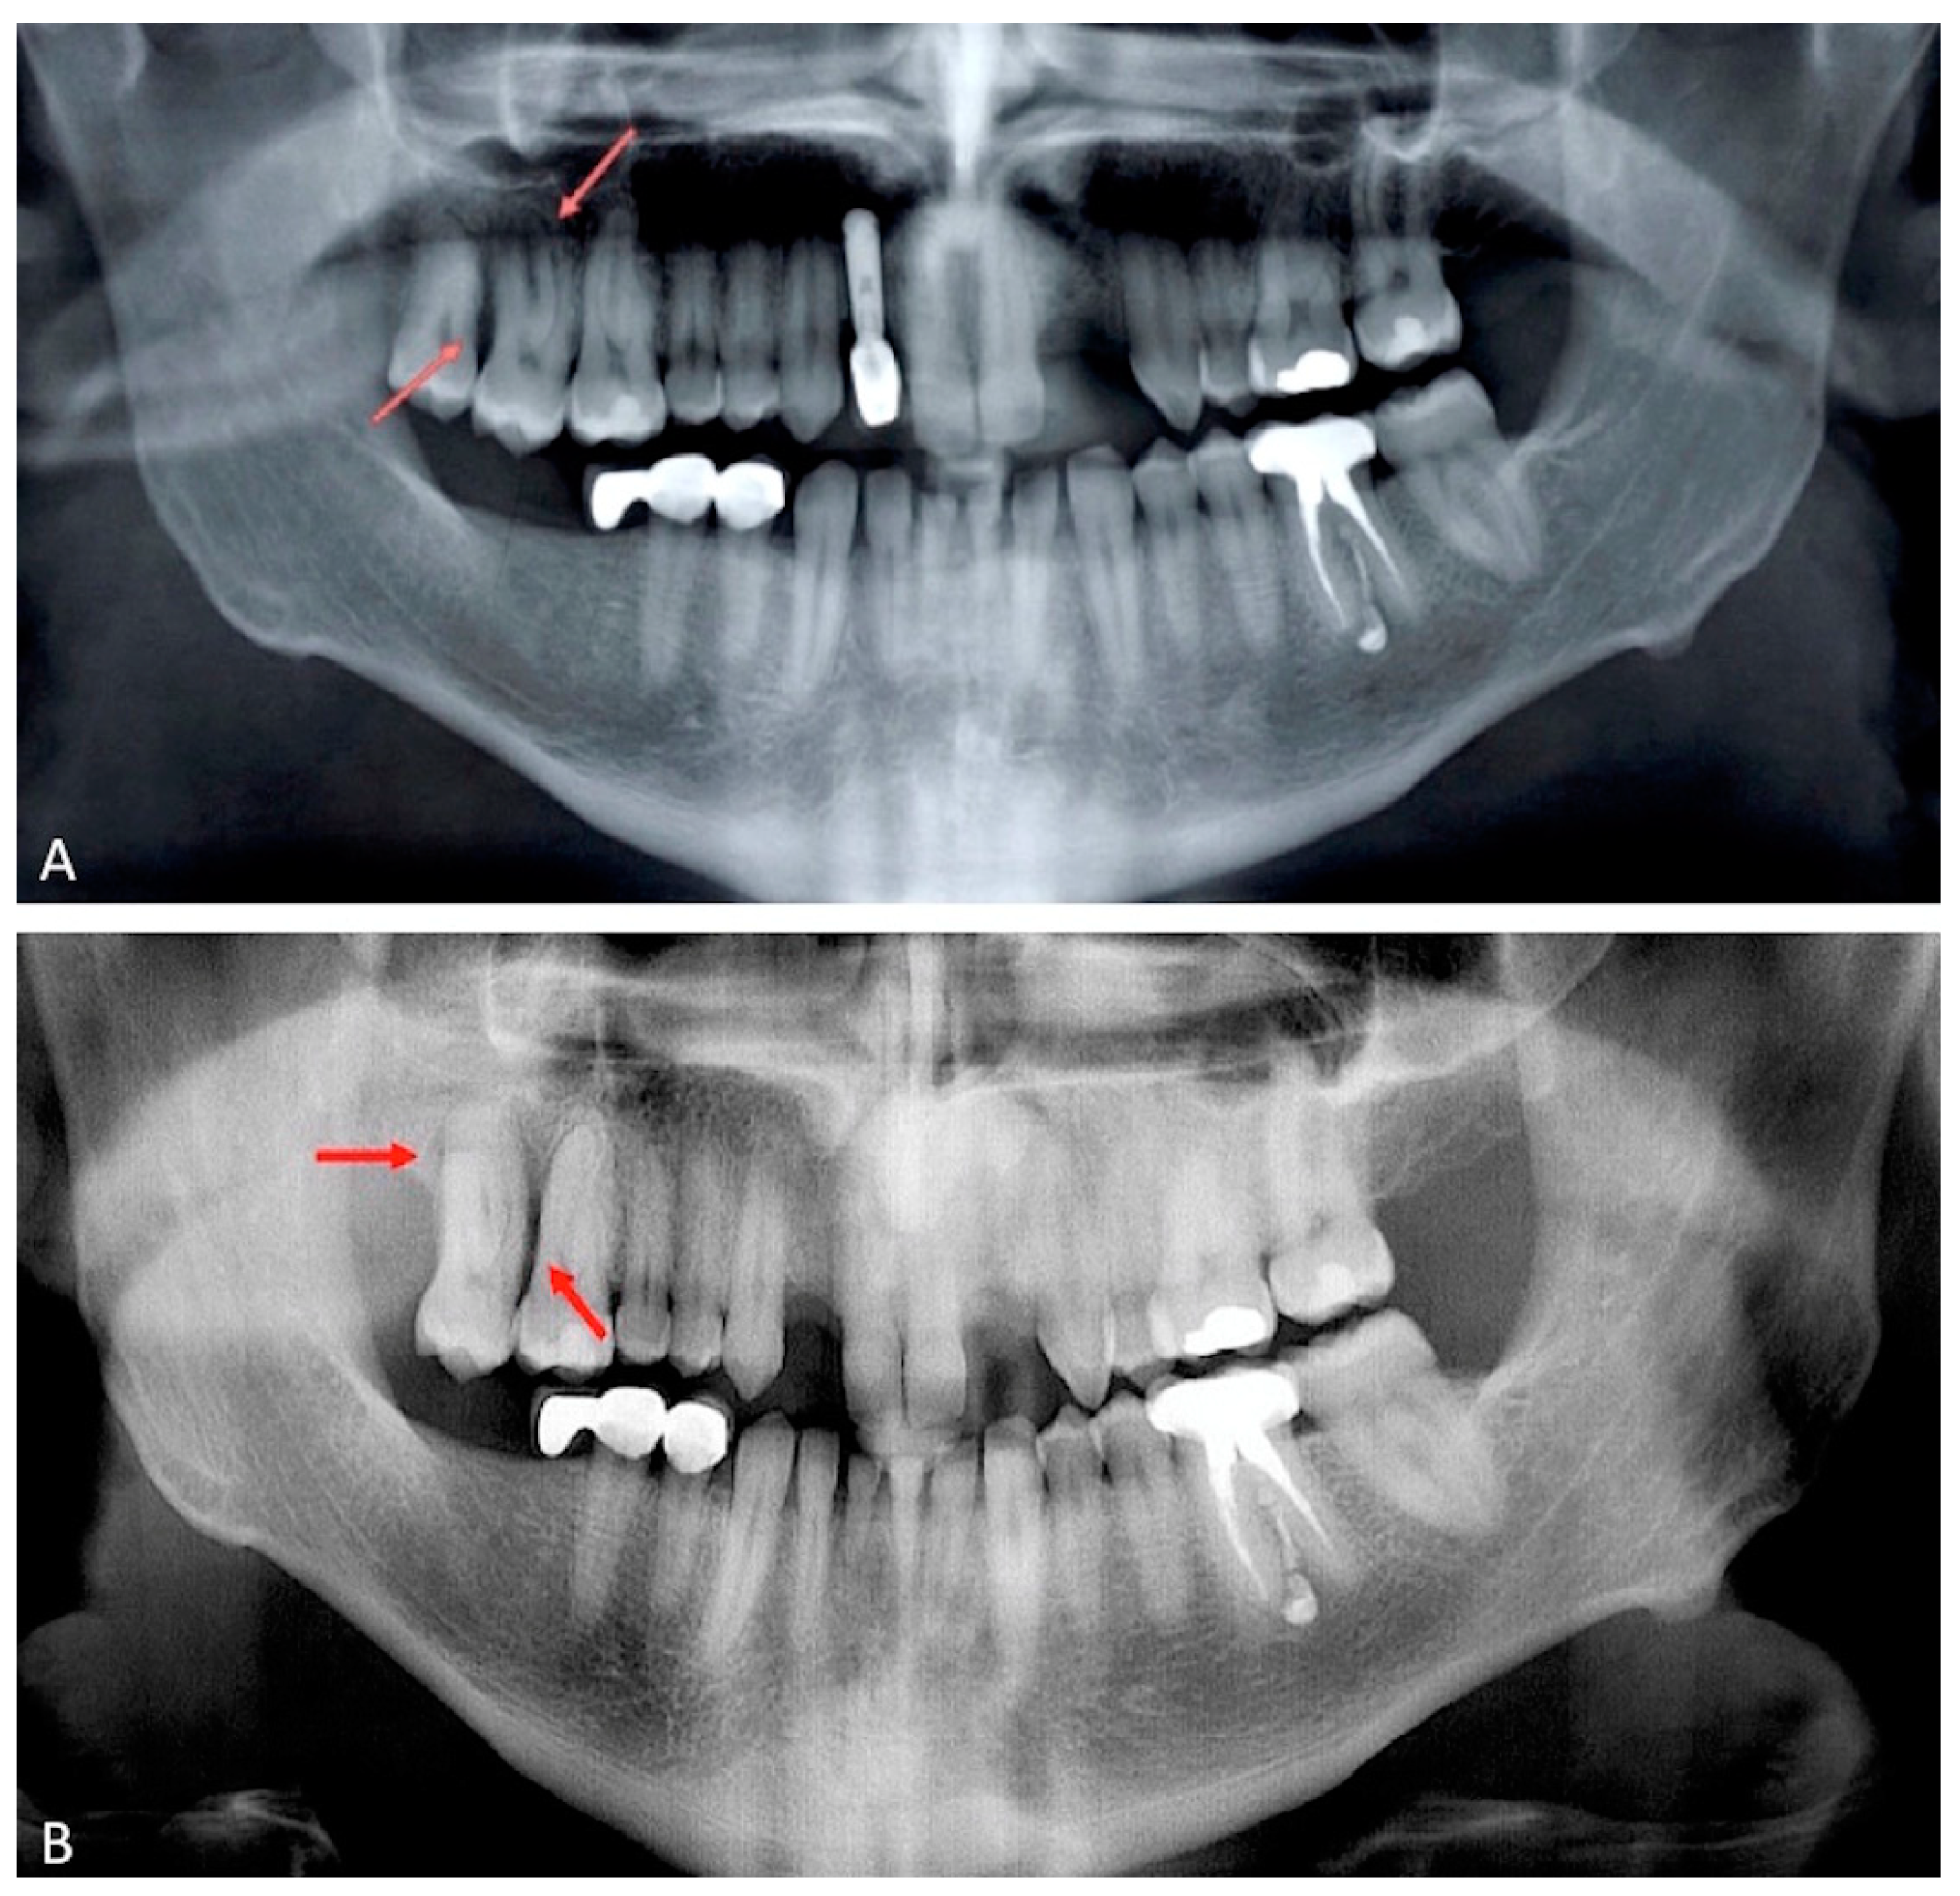

2.1. Case Presentation